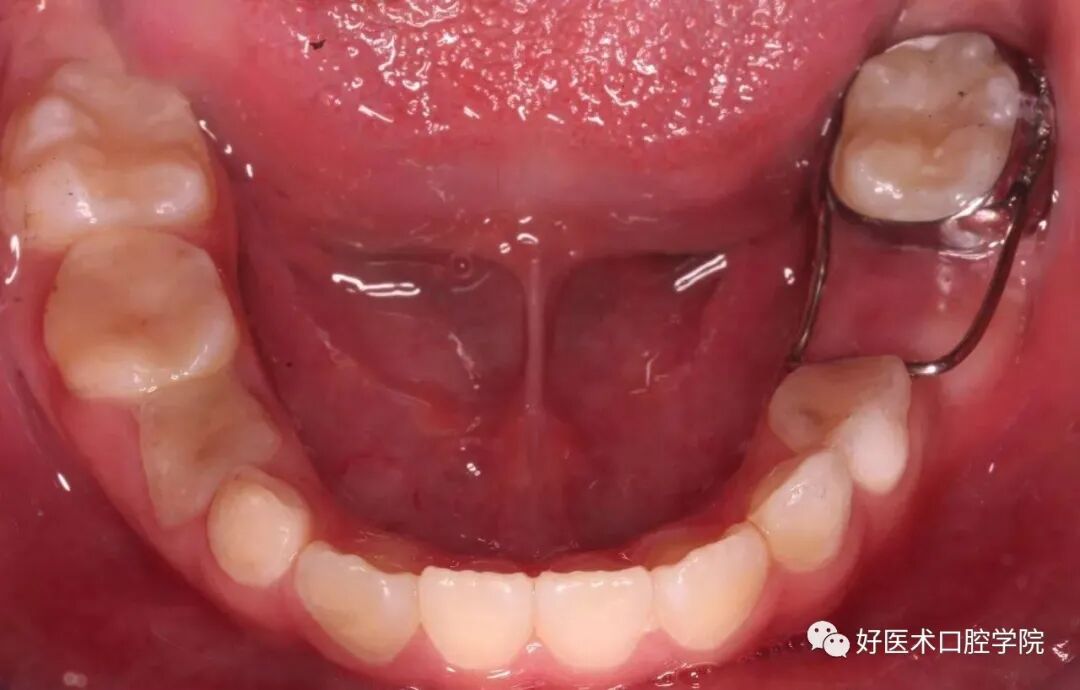

G钻用来处理根管的上端

G钻用来处理根管的上端,常规用32mm的,28mm虽然在后牙操作方便,但因工作端较短、柔性差,所以只要顾客的张口度正常,尽量用32mm的。